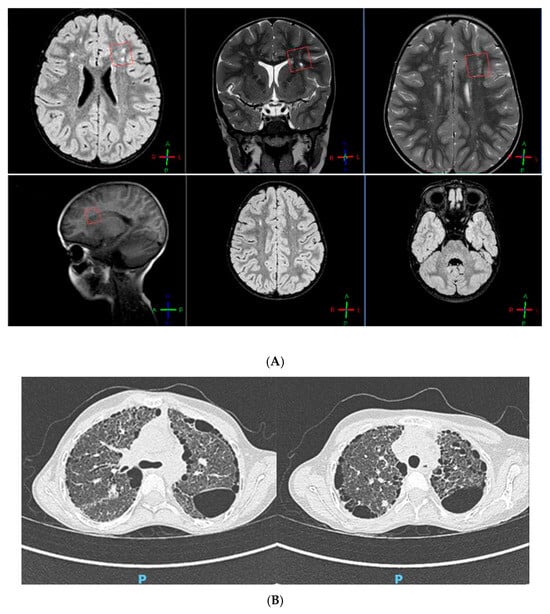

Our patient was an 11-year-old girl, the only child of non-consanguineous, healthy parents. She was born at term (40 weeks of gestation), with a weight of 2.880 kg (15th centile). No anomalies were observed at the transfontanellar ultrasound screening. Her mother referred lactation difficulties (weak sucking reflex) due to muscular hypotonia. Consequently, the girl developed failure to thrive. At 1-month-old age, she was hospitalized for a urinary tract infection. She also started to suffer of frequent upper airway infections, associated with bronchospasm. In the first years of life, a delay in reaching motor development milestones was detected (walking was achieved at 21 months). Hence, by the age of 2, the girl underwent her first brain magnetic resonance imaging (MRI), which showed signs of leukomalacia; then, a neuropsychiatric evaluation and an EEG were performed, with normal results. Given the co-presence of poor growth and psychomotor retardation, chromosome analysis was carried out: karyotype was normal (46, XX), while the Chromosomal Microarray Analysis (CMA) identified a paternally inherited microduplication of the 19q13.41 region, with no pathogenic significance. At the age of 6, a brain MRI was repeated, showing “white matter lesions in the fronto-temporo-parietal regions, encysted perivascular spaces and mega cisterna magna” (Figure 1A).

Figure 1.

(A) Brain MRI showing leukoencephalopathy. (B) Thoracic CT scan showing “ground glass” and “honeycomb” patterns.

An echocardiographic assessment revealed “the presence of ascending aortic ectasia and a systemic-to-pulmonary small collateral vessel, causing a left-to-right shunt with no hemodynamical relevance”. At 7 years old, the girl had a moderate restrictive ventilatory failure (FEV1 52%, FVC 51%, FEV1/FVC 101%). The 6 min walk test (6MWT) showed a decreased functional capacity with exercise-induced oxygen desaturation. Laboratory tests stressed a chronic condition of leukocytosis, hypoalbuminemia (microcytic anemia), and hypergammaglobulinemia; in addition, a persistent alteration of the hepatic enzymes values was reported. No hearing impairment was detected at the audiometry. Myopic chorioretinitis was observed at the fundoscopy. The orthopedic examination stressed the presence of bilateral flatfoot, scoliosis, and knee osteopenia. Based on the medical history marked by frequent respiratory infections and chronic cough, at the age of 10, the patient had a thoracic computed tomography (CT) scan, describing “lung fibrosis (ground glass pattern) with several subpleural cysts (honeycomb pattern), heterogeneously distributed”. As confirmation of these findings, spirometry was re-performed, highlighting a severe restrictive pulmonary insufficiency (FEV1 24%, FVC 27%).

After 18 months of treatment with Nintedanib (25 mg B.I.D.), her respiratory function remained stable (FEV1 26%, FVC 28%). Likewise, a thoracic CT scan was repeated, pointing out a very slight enlargement of the already-known bronchiectasis and cysts (Figure 1B).